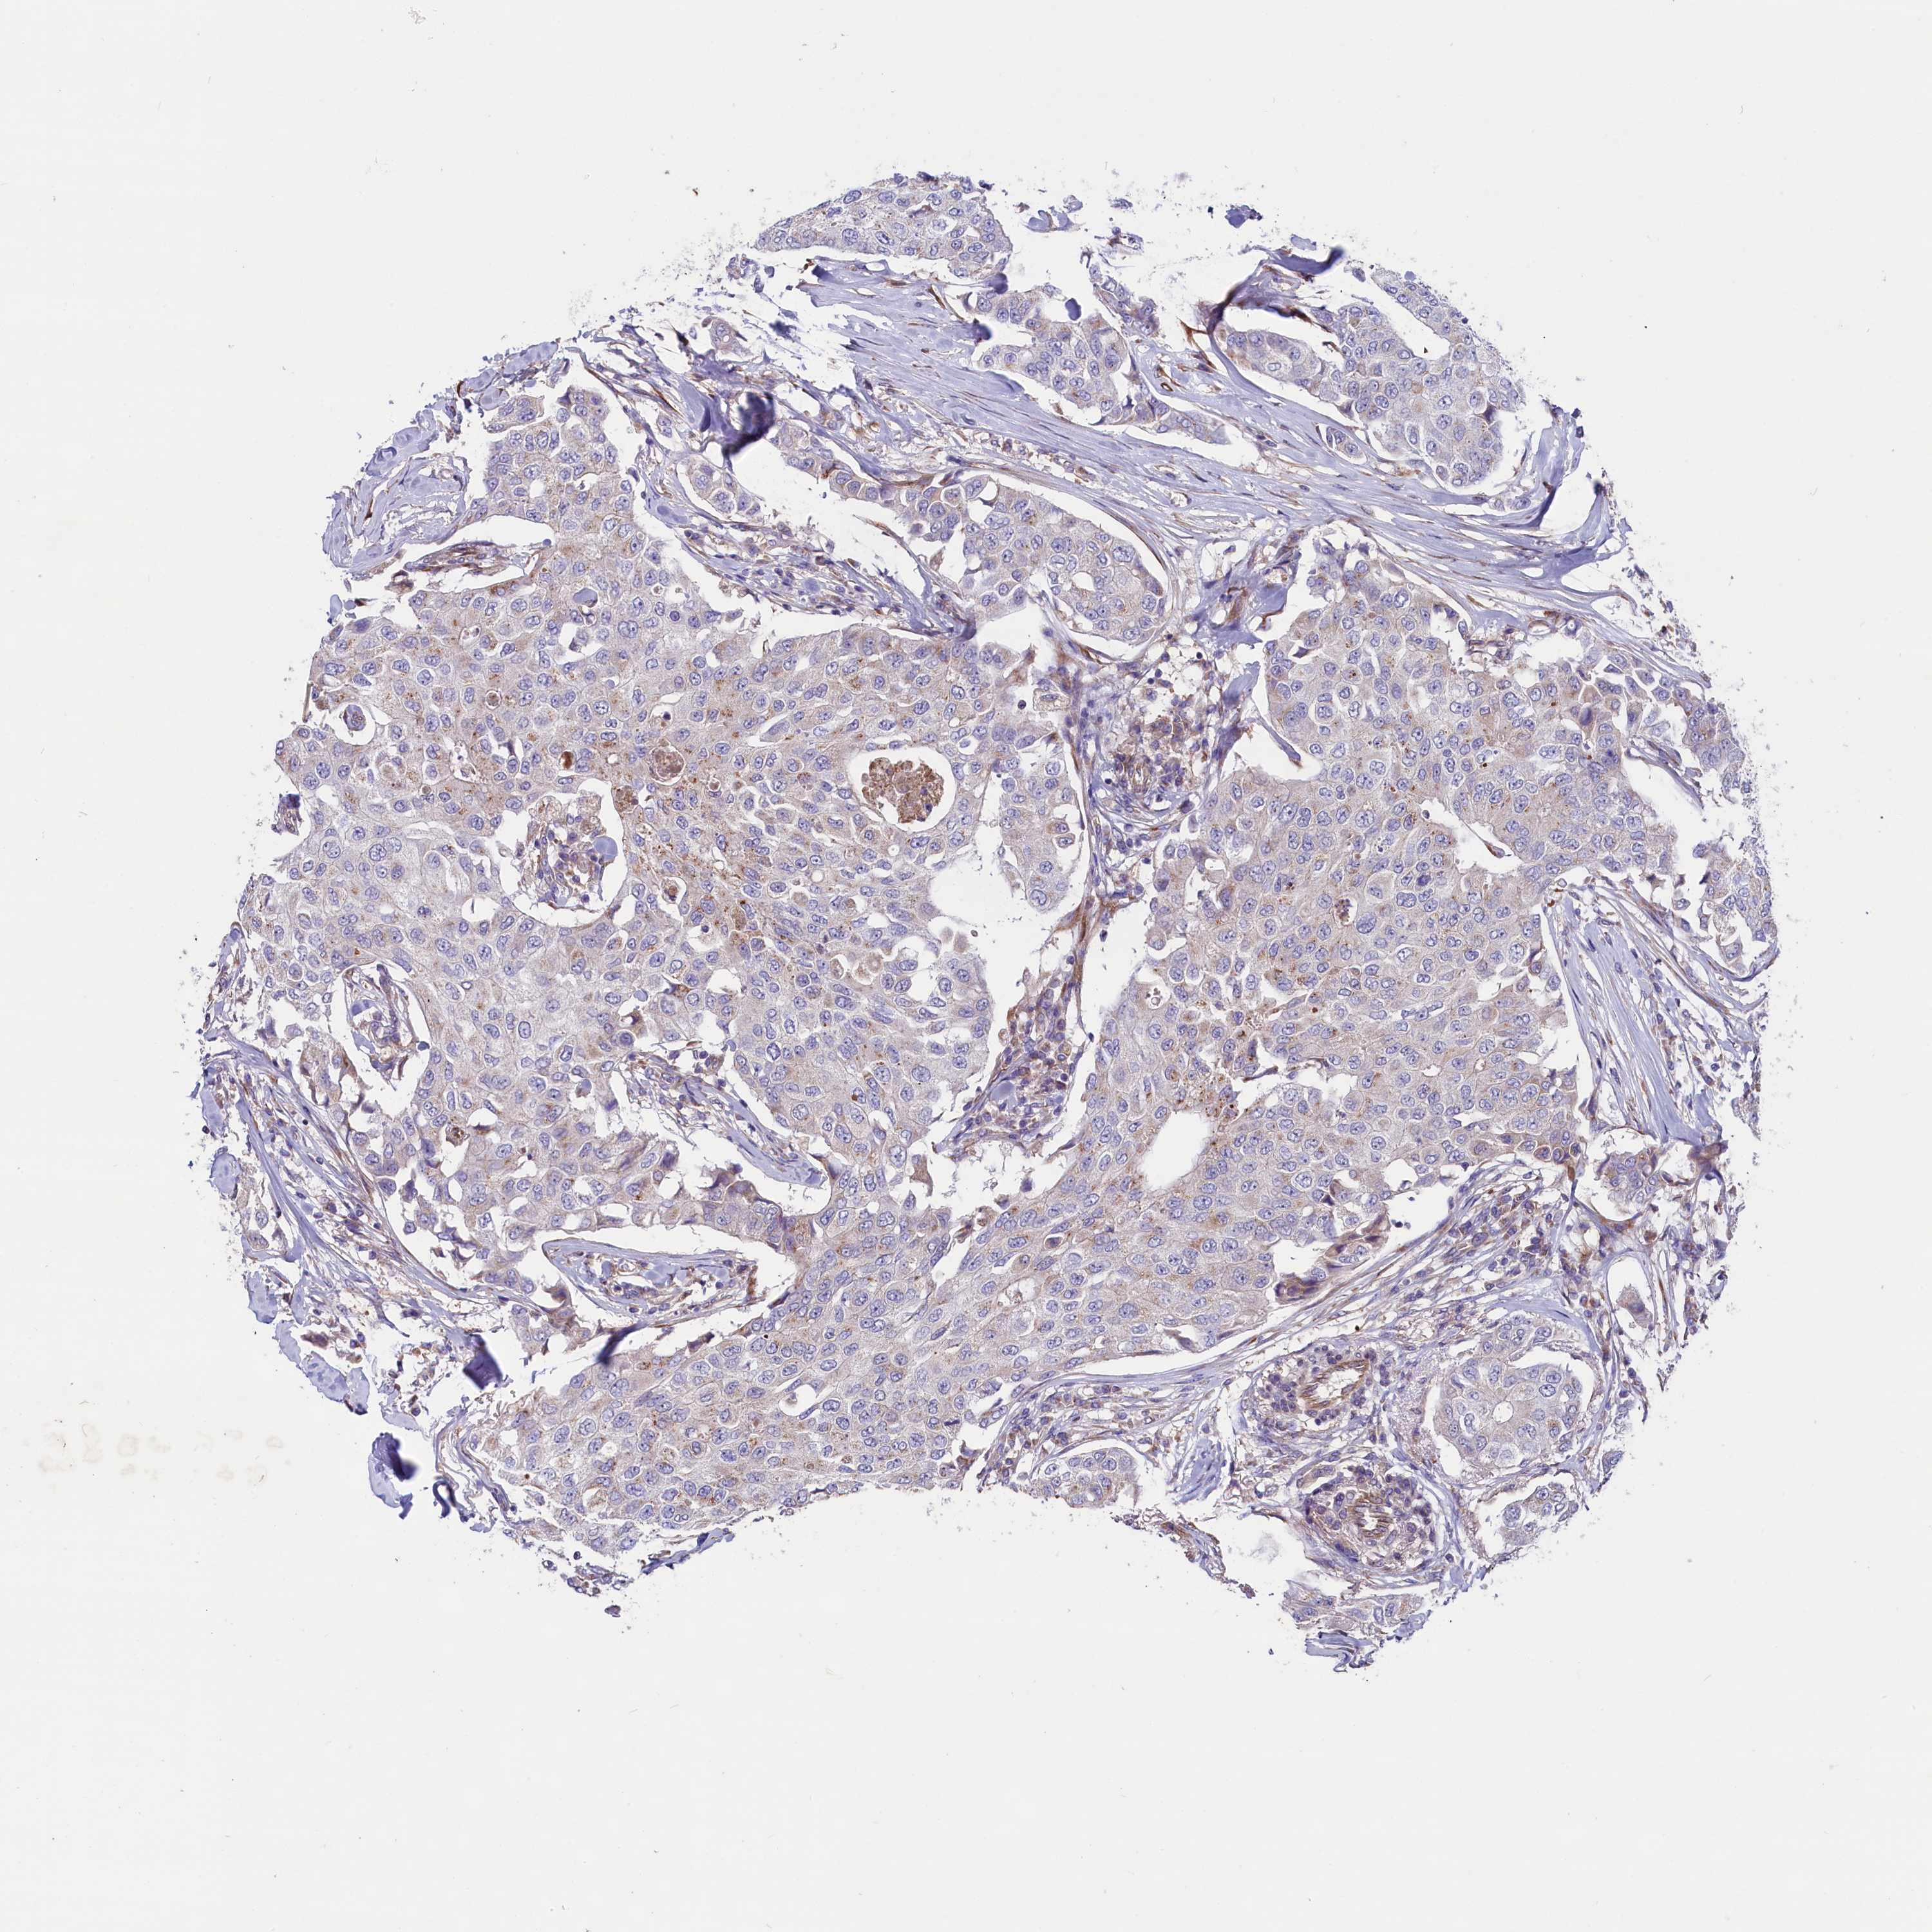

CANCER BREAST CANCER Show tissue menu

BRCA TCGA BRCA VALIDATION PROTEIN EXPRESSION